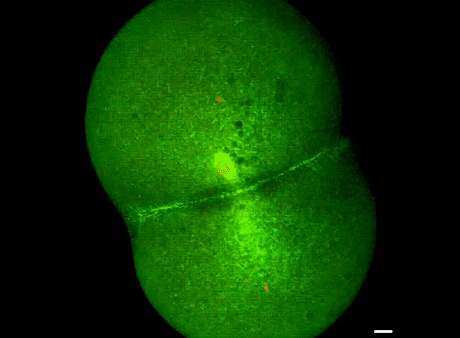

人体大约50万亿个细胞,都从一个受精卵分裂而来。受精卵在刚开始阶段,一分二、二分四、四分八…

斑马鱼受精卵分裂过程

但是,对正常细胞来说,从某个时间开始,这种无限分裂的开关被关了,细胞分化出不同类型,神经细胞、皮肤细胞、肌肉细胞等等,这些细胞有个共同点,寿命一到就得死亡(暂不论生殖细胞)。